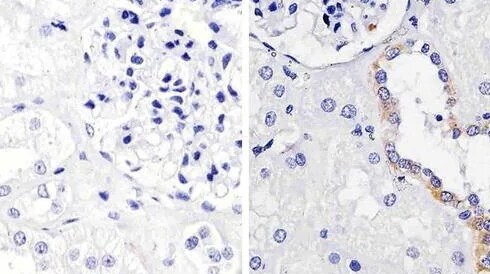

With over 400,000 primary and secondary antibodies from the most reliable and innovative life sciences suppliers, the Fisher Scientific channel carries the industry’s largest selection of antibodies for life sciences applications. Whether you’re performing ELISA or flow cytometry, using western blot methods to identify your target of choice, or multiplexing with fluorescently conjugated antibodies, you’ll find the right antibody in our collection.